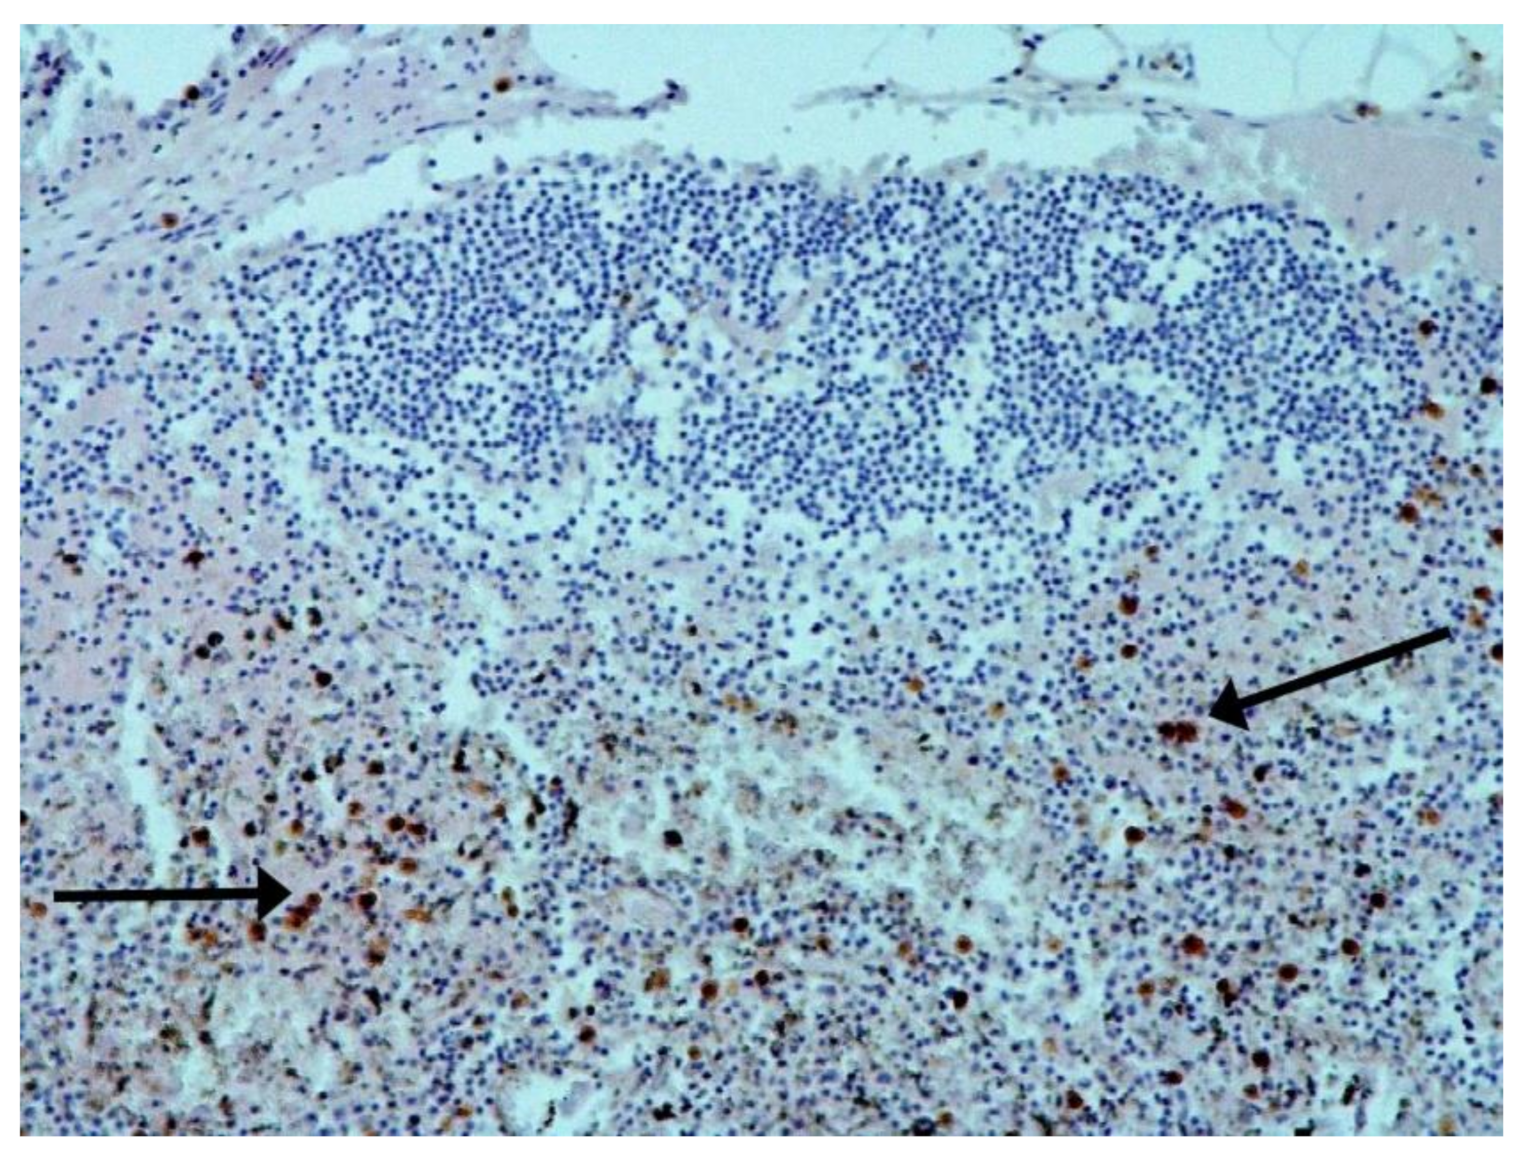

The hallmarks of apoptosis (according to expression of caspase-3) were revealed in the lungs, lymph nodules, and other organs, predominantly in the area with the small granular rhexis (Figure 4 and Figure 5.) The possibility of developing a generalized infection with damage to other organs is evident. Alterative and necrotic changes were seen in parenchymal cells. Sometimes we noted their changes in the nuclei of the cells in the lymph nodes, intestines, soft meninges, heart, pancreas, kidneys, and spleen. We succeeded in detecting spike and nuclear antigen of the virus in the lymph nodes (Figure 6), pancreas, brain (Figure 7), and adrenals. We described certain lesions in the adrenals that are probably associated with the SARS-CoV-2 virus [25].

Figure 4. Caspase-3 (arrows) in lymph node. ICH ×100.